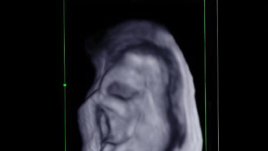

4 строги предписания как бременните да се къпят във вана Полезна ли е ваната през бременността 22.10.2012 | Надежда Маринова